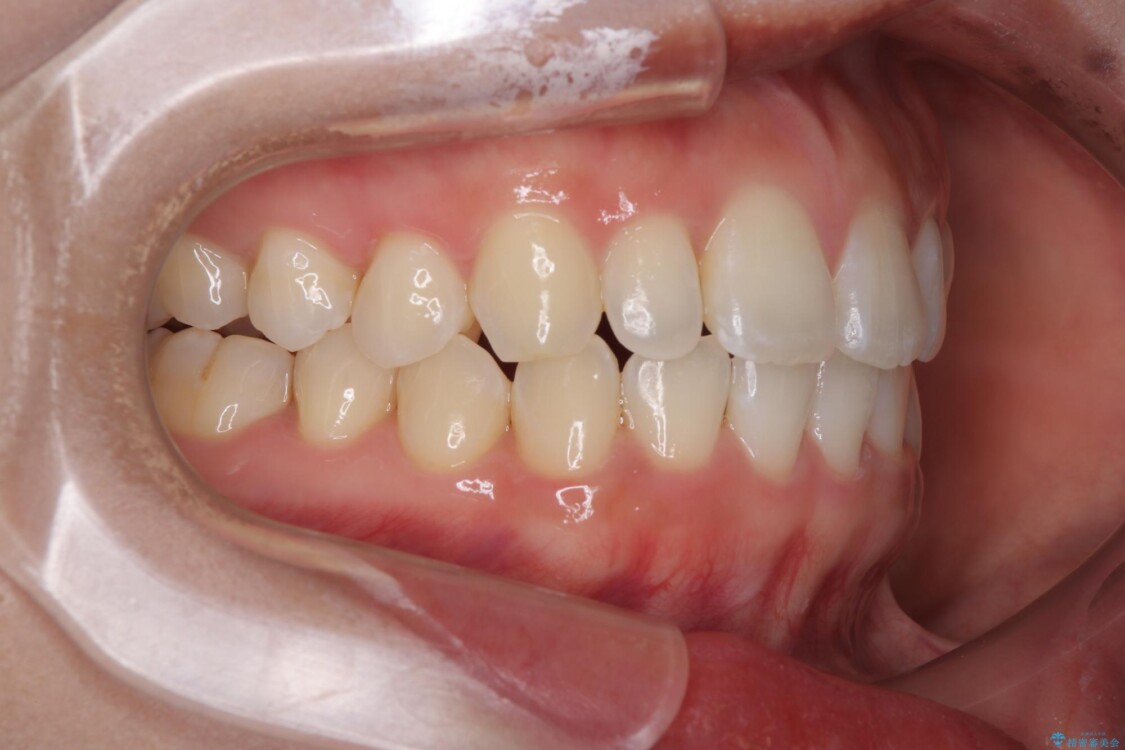

前歯が自然なアーチにきれいに並び、正中(上下の中心線)も整い、咬み合わせも良好です。

側方拡大することで、非抜歯であるにも関わらず前歯が前方に出ることなく、バランスの良い仕上がりとなりました。

治療後

• 目立ちにくい表側装置で1年完了!狭いアーチを側方拡大し前歯のデコボコを整えた症例 治療後画像